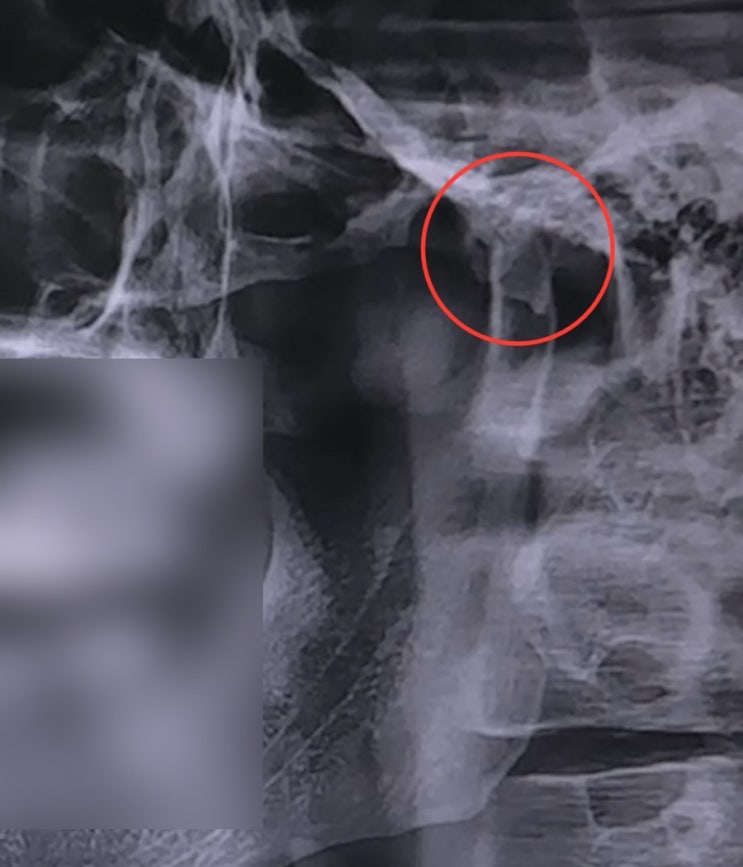

청력검사 받고 왔숩니다 + 외측익돌근

안녕하세요, 페퍼입니다??. 지난 글에 턱 때문인지 귀가 먹먹하다고 썼었는데, 아무래도 확인을 해보...

턱의 긴장과 턱관절, 치아 교합, 그리고 난청

안녕하세요 페퍼입니다??. 제가 요즘 턱이랑 치아 교합 때문에 고생 중이에요. 그래서 기록용으로 일...